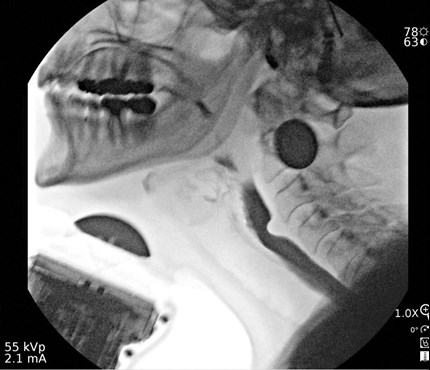

Patient undergoing simultaneous swallowing fluoroscopy with ultrasound and demonstrating a cricopharyngeal bar in order to diagnose cricopharyngeal muscle dysfunction (CPMD).

CPMD refers to impaired relaxation of the upper oesophageal sphincter (UOS). The cricopharyngeus muscle may exhibit hypertrophy, incomplete relaxation or failure to relax – detectable via fluoroscopy, high-resolution manometry or electromyography. The UOS regulates flow both ways – swallowing (‘north-to-south’) and reflux (‘south-to-north’). This sensorimotor complexity remains incompletely understood, yet it underscores how CPMD profoundly affects quality of life. Dysphagia evaluation focuses on both efficiency and safety. Efficiency can be trained, often by a speech language pathologist, with strengthening exercises such as the Masako manoeuvre. Safety, however, is a measure of aspiration risk, significantly impacting quality of life by dietary restrictions such as food thickener, or worse, alternative nutrition such as gastric feeding tubes (completely bypassing our sensory experience of taste and texture of food we consume).

CPMD is a confluence of both pharyngeal and oesophageal dysphagia related to both sensory feedback and motor response. Swallowing fluoroscopy is the most used diagnostic tool to confirm CPMD in patients with obstructive symptoms. However, the variability in imaging quality, number of swallows and frame rates yield poor reproducibility. Furthermore, availability of swallowing fluoroscopy limits patient access.